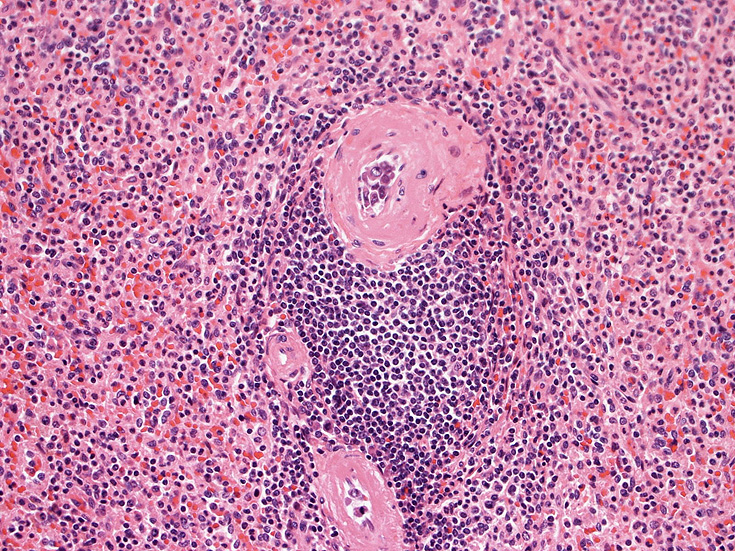

脳梗塞病変の脳生検組織

梗塞組織近傍の細血管内に腫瘍細胞が認められる.